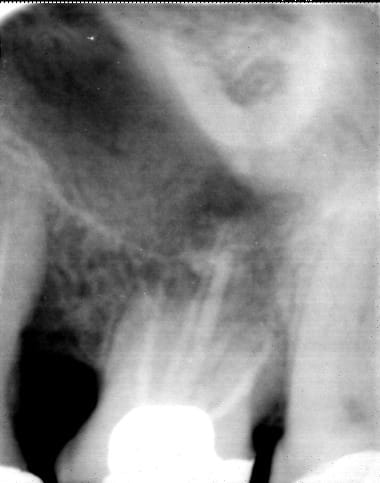

A 9 mois, pas de soucis de la part du patient...

00000019 iq3yan - Eugenol

c'est bien mais le but c'est quoi narik? Tu as une fonte paro importante des deux cotés. Ok ton TR est un succes a court terme et peut etre a long terme mais vu la quantité d'os qui te reste, penses tu attendre l'atteinte de furcation, ou tu preferes que la racine distale flotte dans le vide? Comment ce patient fait il pour brosser sa poche paro qui si la radio n'est pas trop defilée lui laisse 3 à 4 mm d'os autour de son apex?

quand le reste de nonos sera parti, l'implant tu le vissera dans quoi ?

bémol : ta radio est défilée mais je ne sais pas de combien donc c'est quand meme trompeur mais dans le cas ou elle ne l'est pas trop, moi je conserve pas désolé.

Cela dit le TR a permis d'assainir l'os et permettra peut etre de faire une extraction imlantation immédiate dans la racine palatine ce qui est une bonne chose.

En bouche la dent ne bouge absolument pas, pas d'inflamation, brossage nickel.

Pour la 25 on a eut un regain d'attache suite au ttt paro.

Comme il y a réévaluation chez le paro dans quelques moi, suite à cela j'en discuterai avec lui, mais on a commencé un truc avec le patient, on va voir sur un an ce que ça donne, pour l'instant on a juste réussi à assainir et avoir une consolidation osseuse, mais jusque quand???